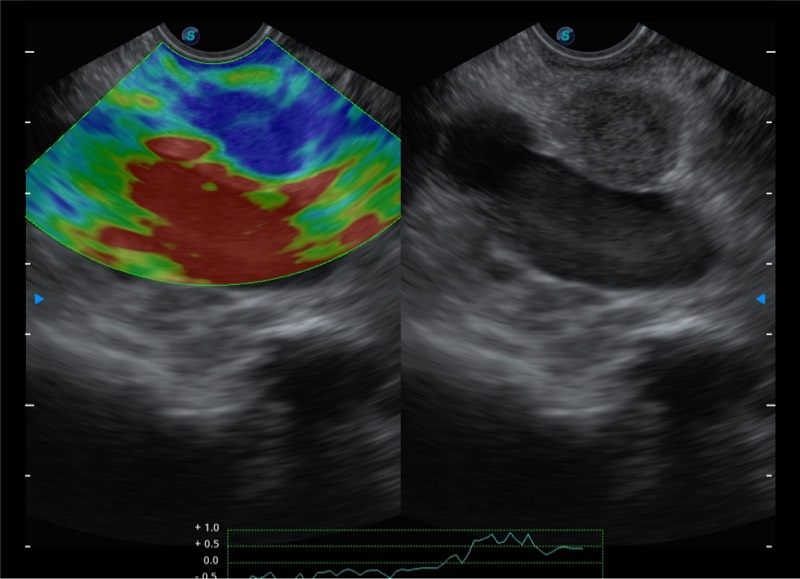

基于二十年的超声技术积累,16877太阳集团提供了最新一代的独立超声主机,在提供高质量图像的同时满足多学科使用。具备常见多普勒技术并提供弹性成像、声学造影等高端影像技术。新一代传感器具有更强的抗干扰能力并减少图像伪影。